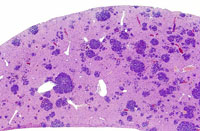

Low magnification of erythroleukemic infiltrates in the liver.

Examples of erythroleukemia in a Tg.AC mouse.